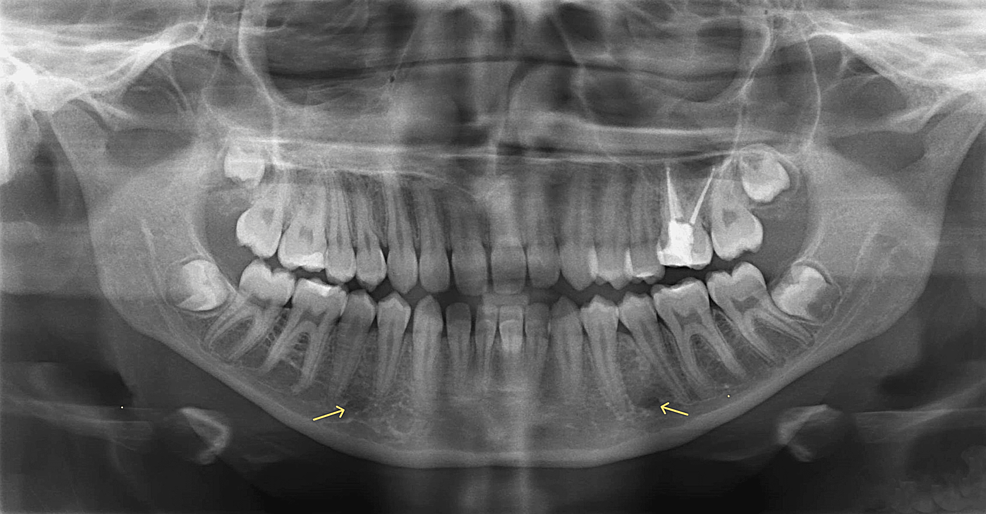

what does panoramic xray show

A wide view of the maxilla, mandible, and pts overall oral and facial structure

what is panoramic xray used to evaluate

dentition and supporting structures

impacted teeth

eruption patterns, growth, and development

disease lesions and conditions of the jaw

trauma

what are the normal anatomic landmarks

bony landmarks of maxilla, mandible, and surrounding strucutures

air spaces and soft tissues seen on pano images